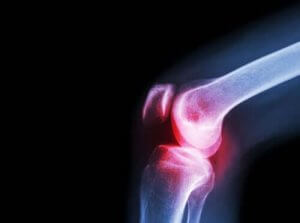

ऑस्टियोआर्थराइटिस (Osteoarthritis)

डॉक्टरों ने इस स्थिति के लिए भी एसिक्लोफेनेक की सिफारिश की है। ऑस्टियोआर्थराइटिस एक अन्य रयूमेटिक बीमारी है जो जॉइंट कार्टिलेज को नुकसान पहुंचाती है।

जॉइंट में एक तरल पदार्थ होता है जिसे सिनोवियल द्रव के रूप में जाना जाता है जो सिनोवियल मेम्ब्रेन का निर्माण करता है। जोड़ों को बनाने वाली हड्डियों के सिरे आर्टिकुलर कार्टिलेज से ढके होते हैं।

जब इस कार्टिलेज को क्षति होती है, तो यह दर्द, कठोरता और विकलांगता का कारण बनता है। इसलिए गठिया से इस बीमारी को अलग करना जरूरी है। इसमें से दूसरा जॉइंट में होनेवाली सूजन के कारण विकसित होता है, न कि कार्टिलेज की क्षति से।

हालांकि, चूंकि वे दोनों दर्द का कारण बनते हैं, इसलिए एसिक्लोफेनेक उन लक्षणों के इलाज में असरदार है जो वे दोनों पैदा करते हैं।